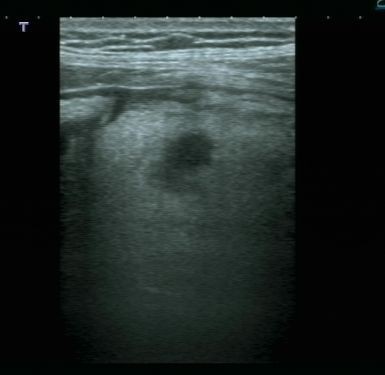

Lo studio medico privato del Dottor Patrizio Stornelli è ad Avezzano è dotato di un'attrezzatura ecografica moderna. Oltre alla ecografia addominale dei parenchimi, si esegue l'ecografia gastroenterolgica ed in particolare l'ecografia del tenue, che consente la diagnosi ed il follow-up particolaremente dei paziente con malattia di Crohn, ma anche l'ecografia del colon. Grazie a questo approccio è possibile scansionare interi segmenti del colon con particolare riguardo alla patologia diverticolare ma anche di indiduare l'appendice e di porre diagnosi di certezza di eventuale appendicite acuta.